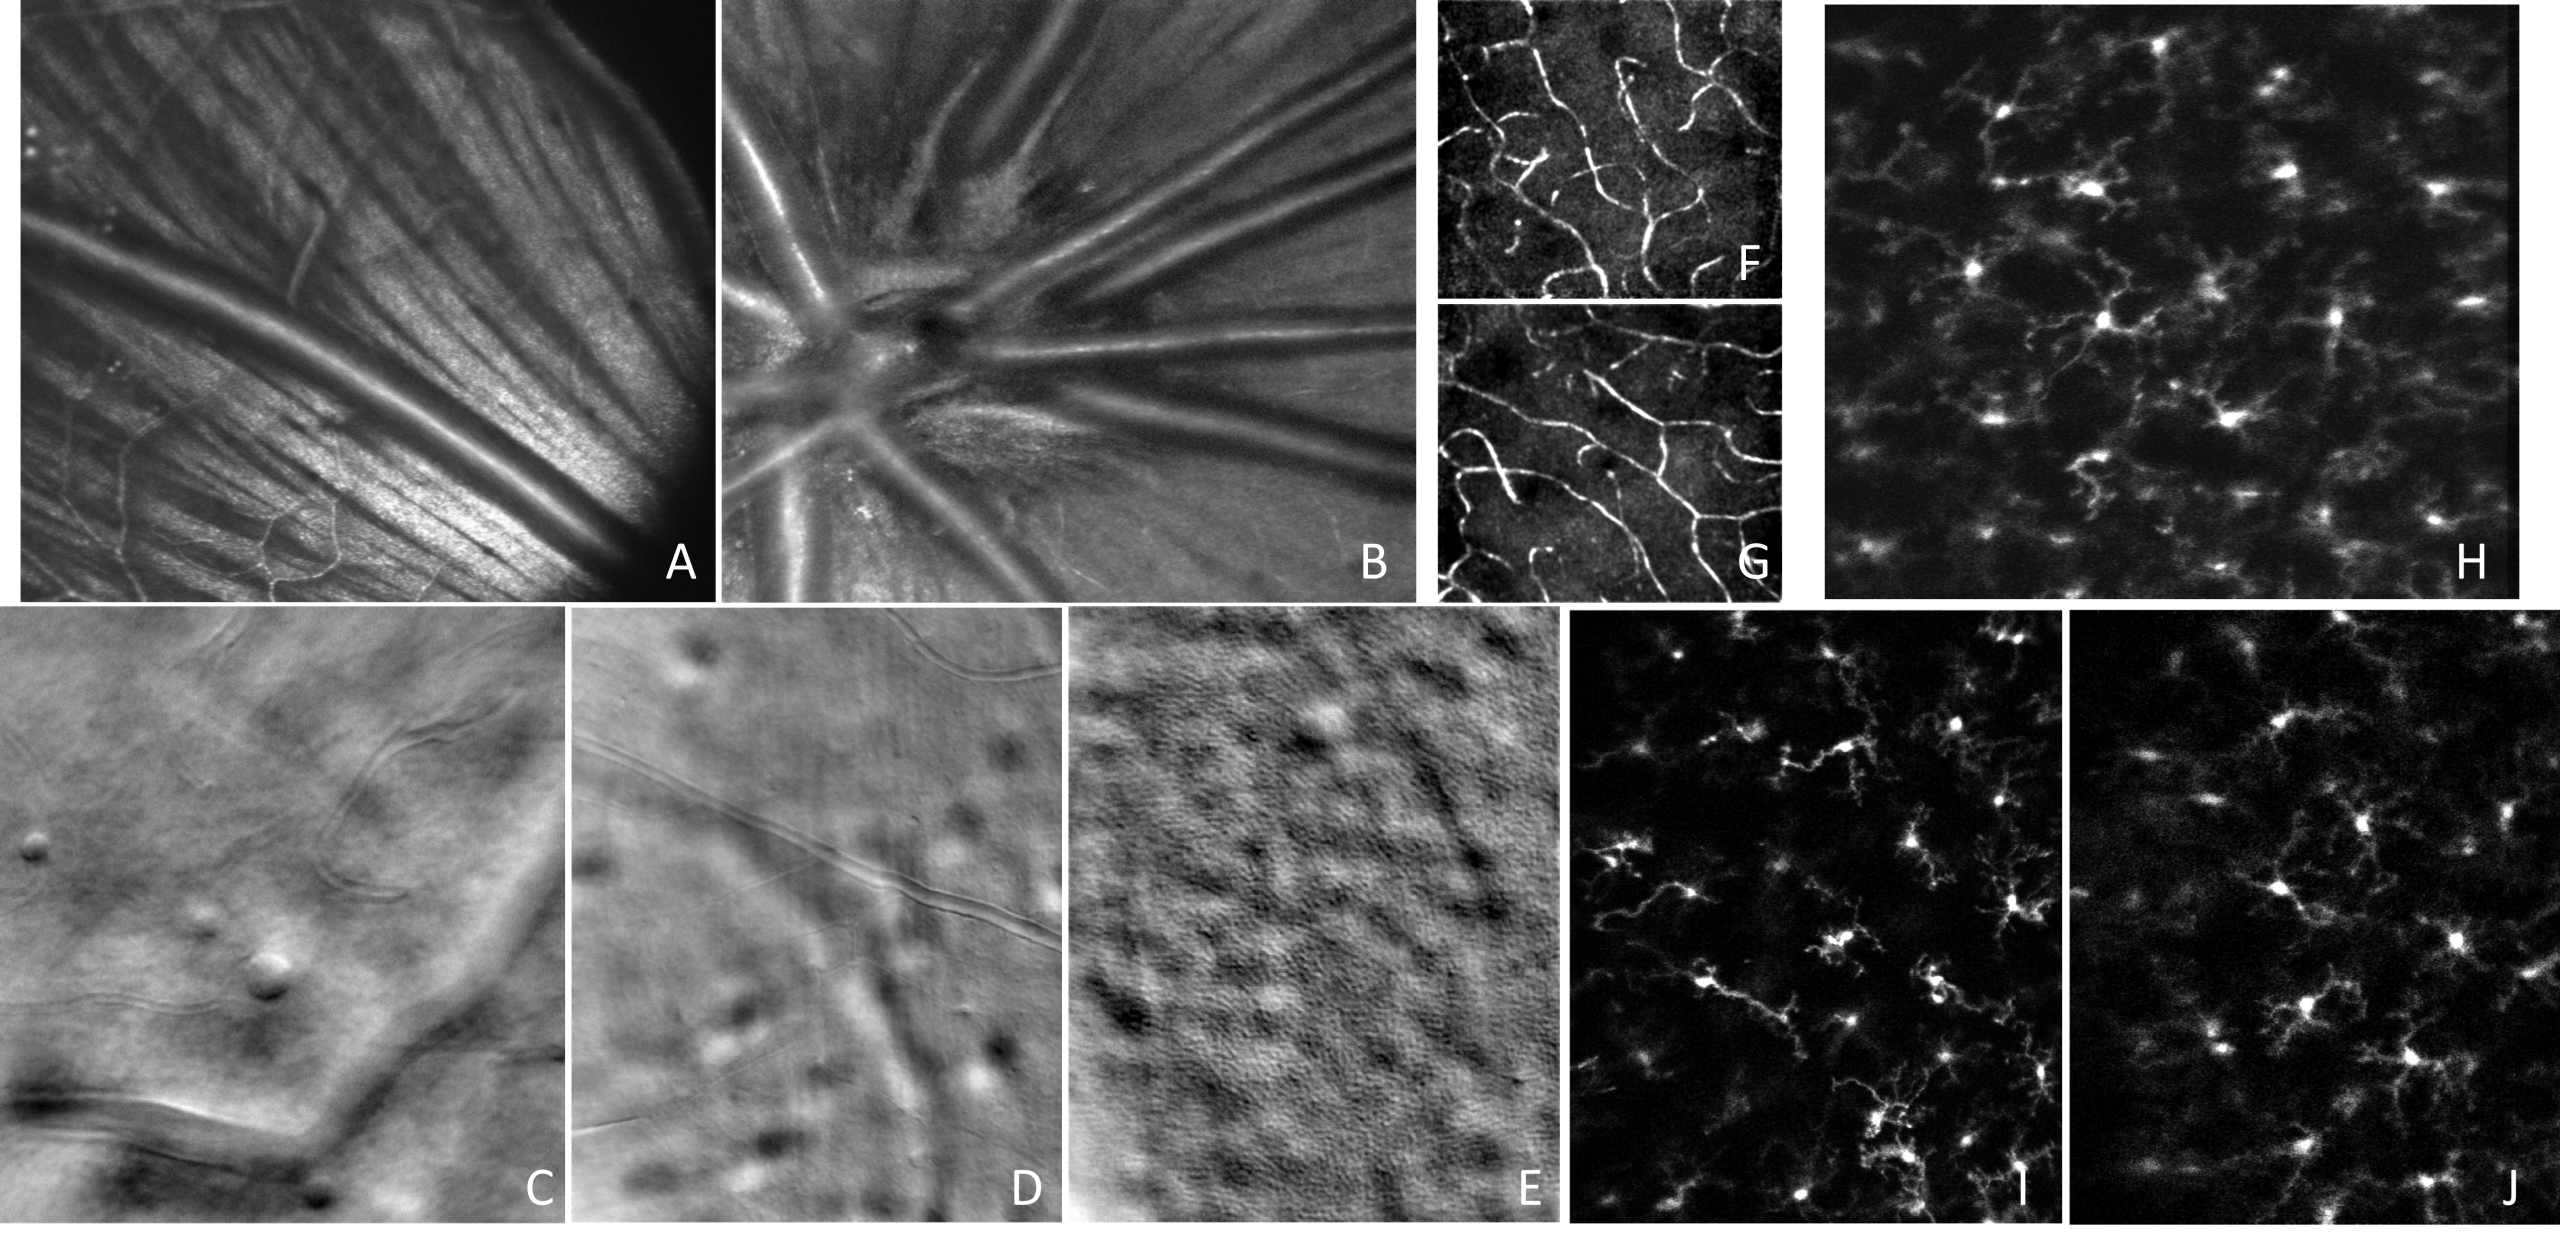

Simultaneous AO-SLO and AO-OCT

Motion Contrast, Phase Gradient, and Simultaneous OCT Images Assist in the Interpretation of Dark-Field Images in Eyes with Retinal Pathology”, Diagnostics, 14(2), 184, (2024)

Confocal, offset aperture, motion contrast, and fluorescence small animal retinal imaging

“High-Resolution Retinal Imaging: Technology Overview and Applications”, Photonics 11(6), 522, (2024)